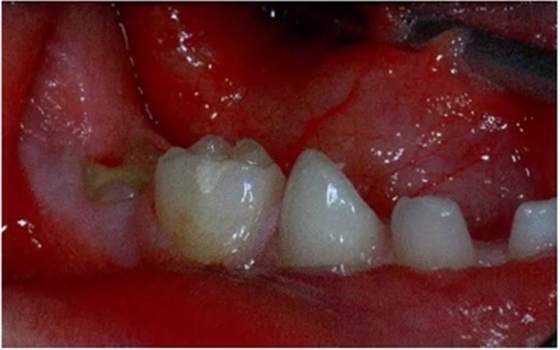

遲發(fā)型乳牙下沉同時(shí)表現(xiàn)為下沉進(jìn)展及根吸收都很緩慢時(shí),通常可以保留的時(shí)間長(zhǎng)一些,甚或是不設(shè)期限地保留。處于一個(gè)并不擁擠的牙弓之中,伴有繼承恒牙胚先天缺失的輕中度下沉牙可以保留下來(lái)并修復(fù)高度以維持其功能。修復(fù)可以使用全覆蓋的樹(shù)脂高嵌體完成(圖7)。這種修復(fù)體能夠恢復(fù)下沉牙的合面高度,防止鄰牙傾斜以及對(duì)合牙伸長(zhǎng)。不過(guò),我們很難預(yù)測(cè)這些牙齒什么時(shí)候脫落,還是會(huì)永久保留下去。與此相反,如果是發(fā)生在需要正畸的擁擠牙弓,那么就應(yīng)當(dāng)拔除這些牙;這一步應(yīng)當(dāng)只是作為正畸治療計(jì)劃的一部分來(lái)完成。

圖7:臨床照片顯示在一顆沒(méi)有繼承恒牙胚的下沉下頜乳磨牙上使用樹(shù)脂堆疊修復(fù)